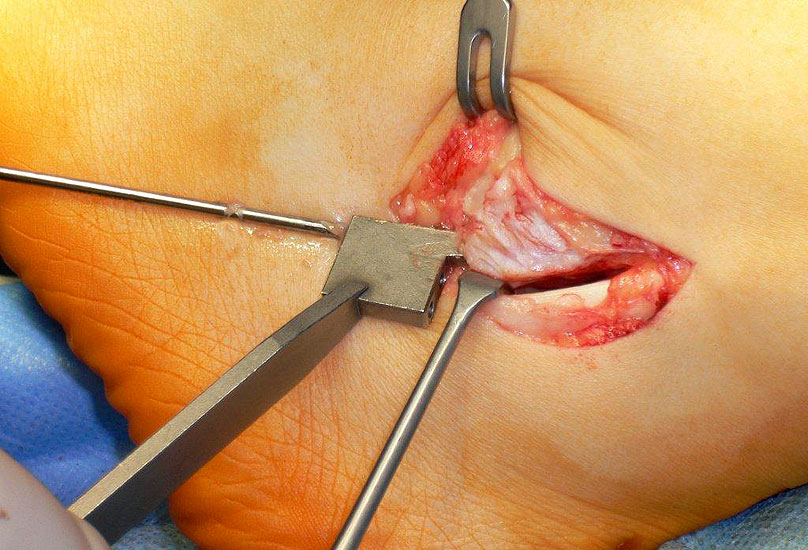

• Ggf. Magnetresonanztomographie des Rückfußes mit Kontrastmittel in Bauchlage und Plantarflexion des Fußes zur Beurteilung der Sehnen und des Bandapparates 20. Die Aussagekraft der MRT ist bezüglich gleichzeitiger Schäden der Sehnen gut. Die Instabilität selbst kann durch eine MRT Untersuchung nicht abschließend ausgeschlossen werden, da Untersuchung oft nicht im Stadium der akuten Luxation durchgeführt wird (Abbildung 3). Dagegen erlaubt die dynamische Untersuchung mit Ultraschall eine präzise Beurteilung der Sehnenstabilität 21.